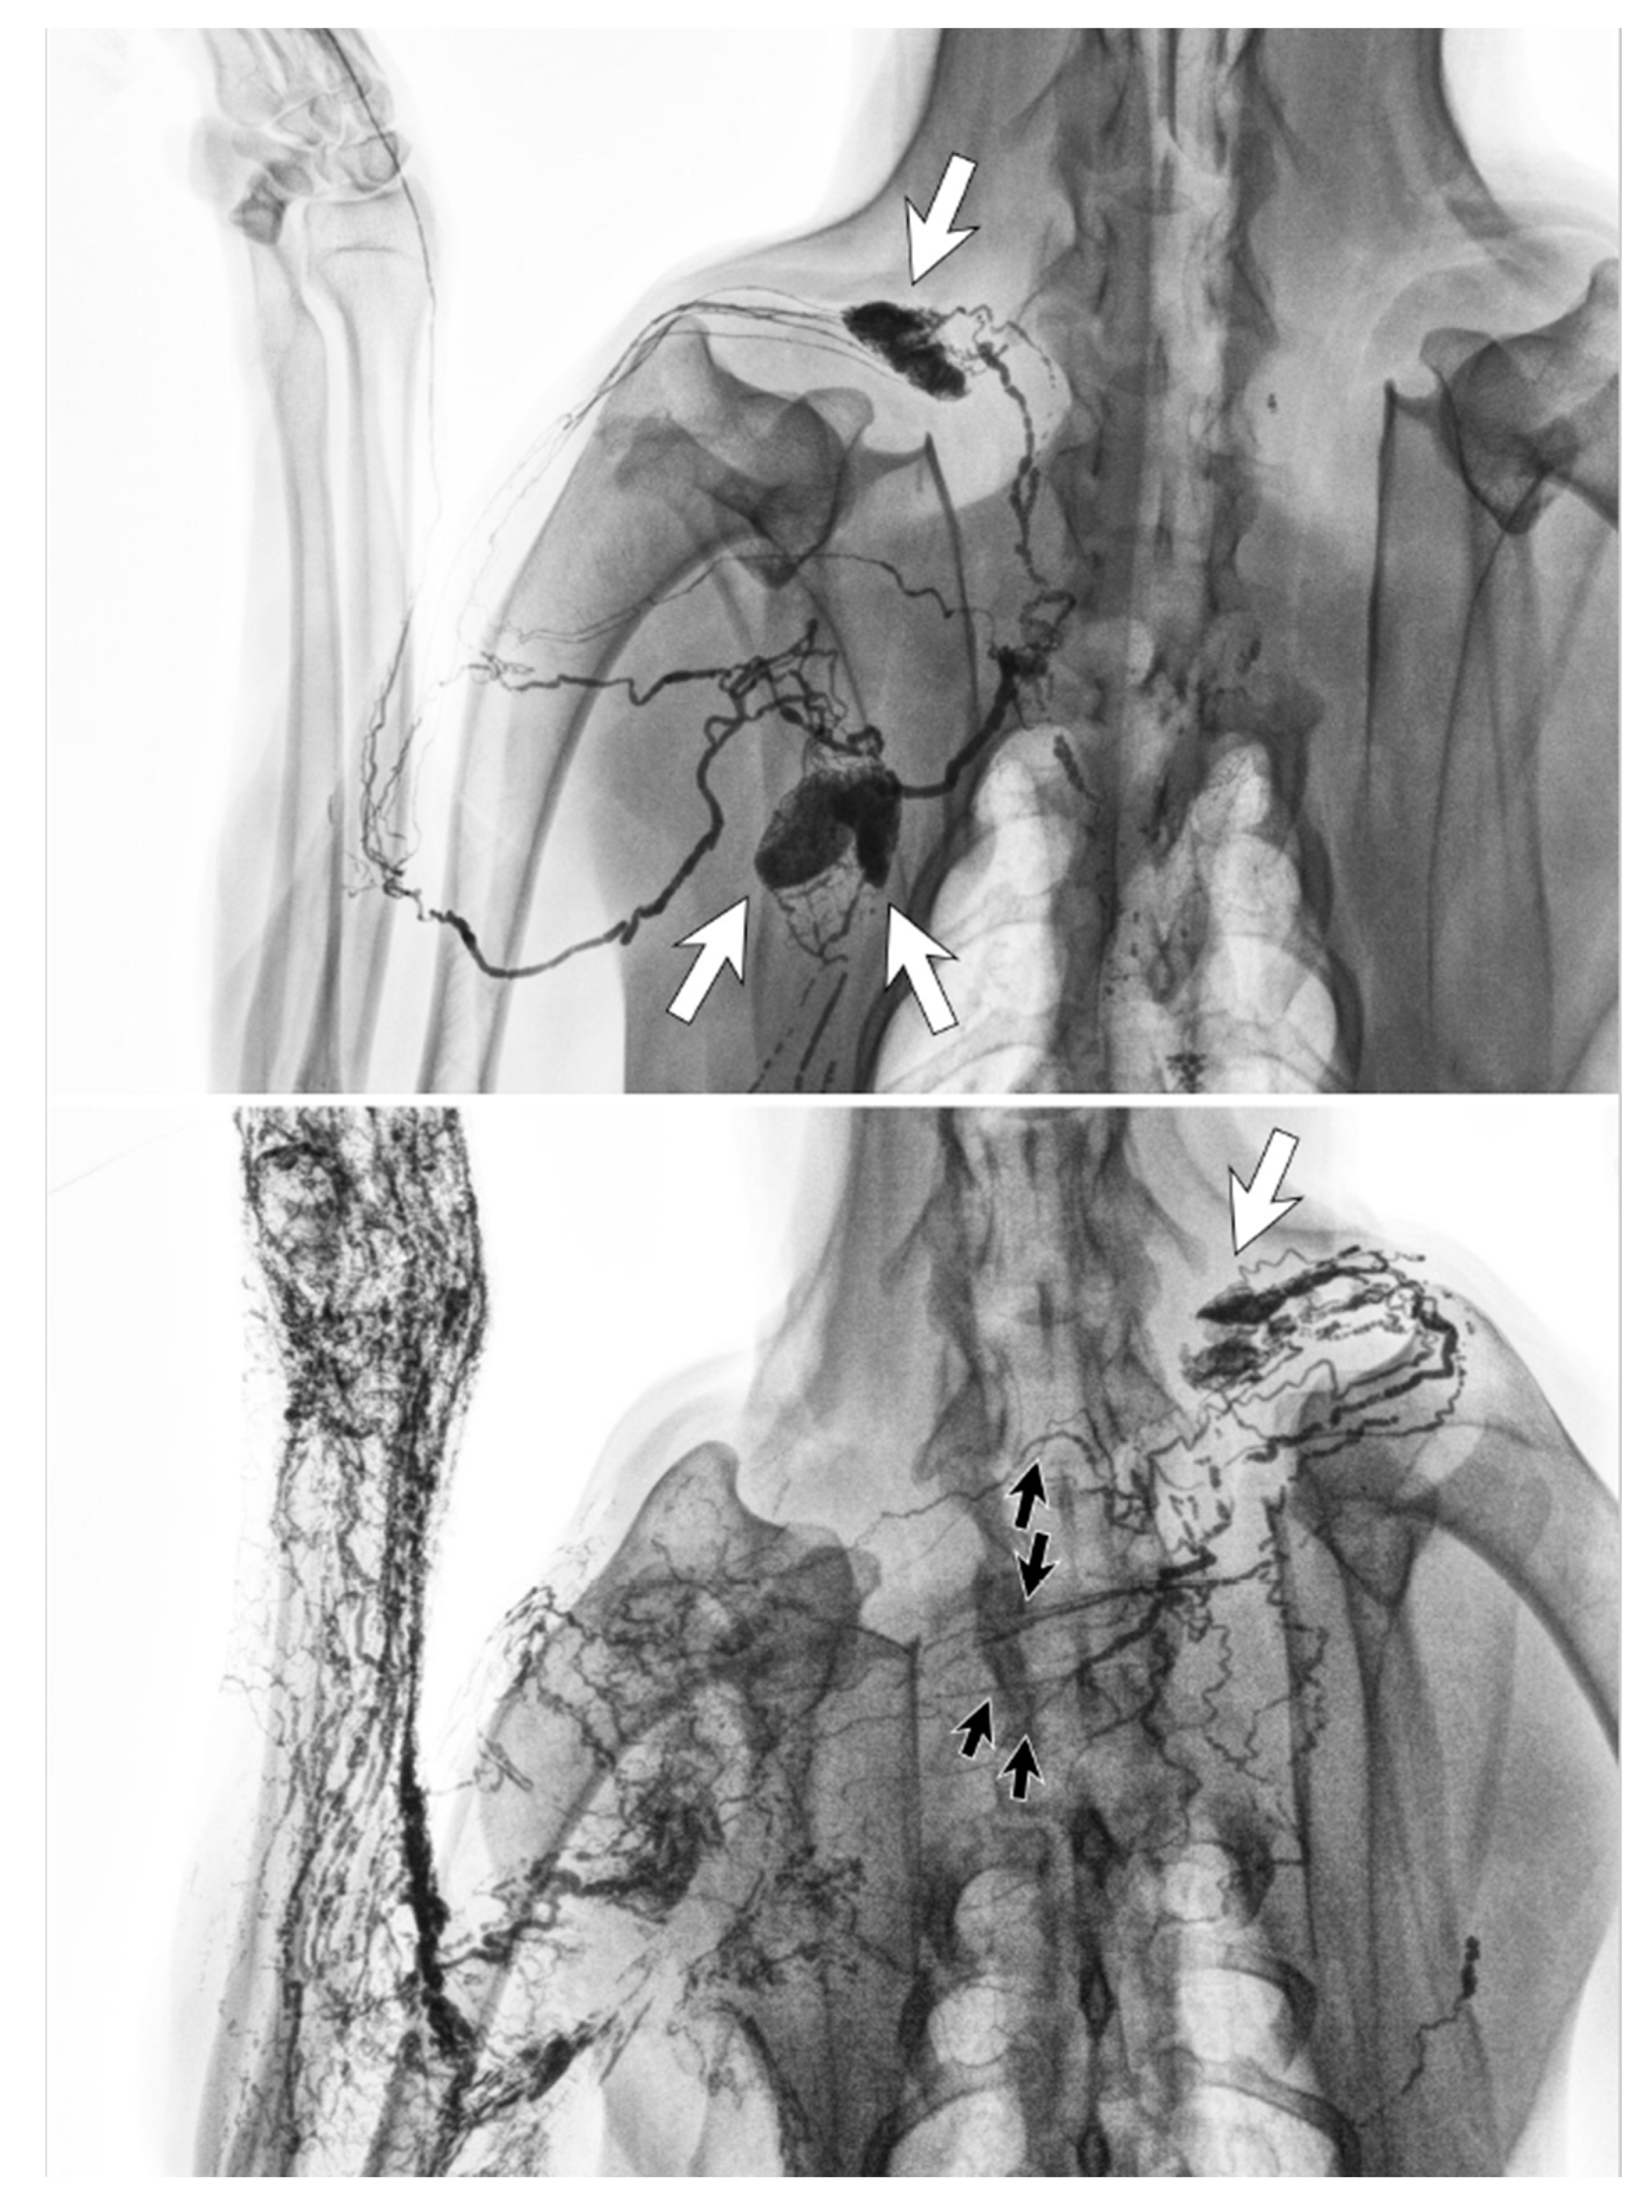

Figure 6.

Lymphangiography images of a canine before lymph node dissection surgery (top) and six months afterwards (bottom). The lymphatic vessels from the left forelimb crossed the front midline and connected to the right cervical lymph node (white arrow) via regenerated lymphatic vessels (black arrows). (Reproduced from [36] with permission.).

Clinical imaging studies using lymphangiography, lymphoscintigraphy and ICG lymphography also found that the lymphatic system in the affected limb could reconnect to the remaining lymph nodes through lymphangiogenesis [38,39,40,41,42]. The location of the remaining nodes varied from the ipsilateral axillary, supraclavicular, internal mammary and contralateral axillary nodes (Figure 7) [42].